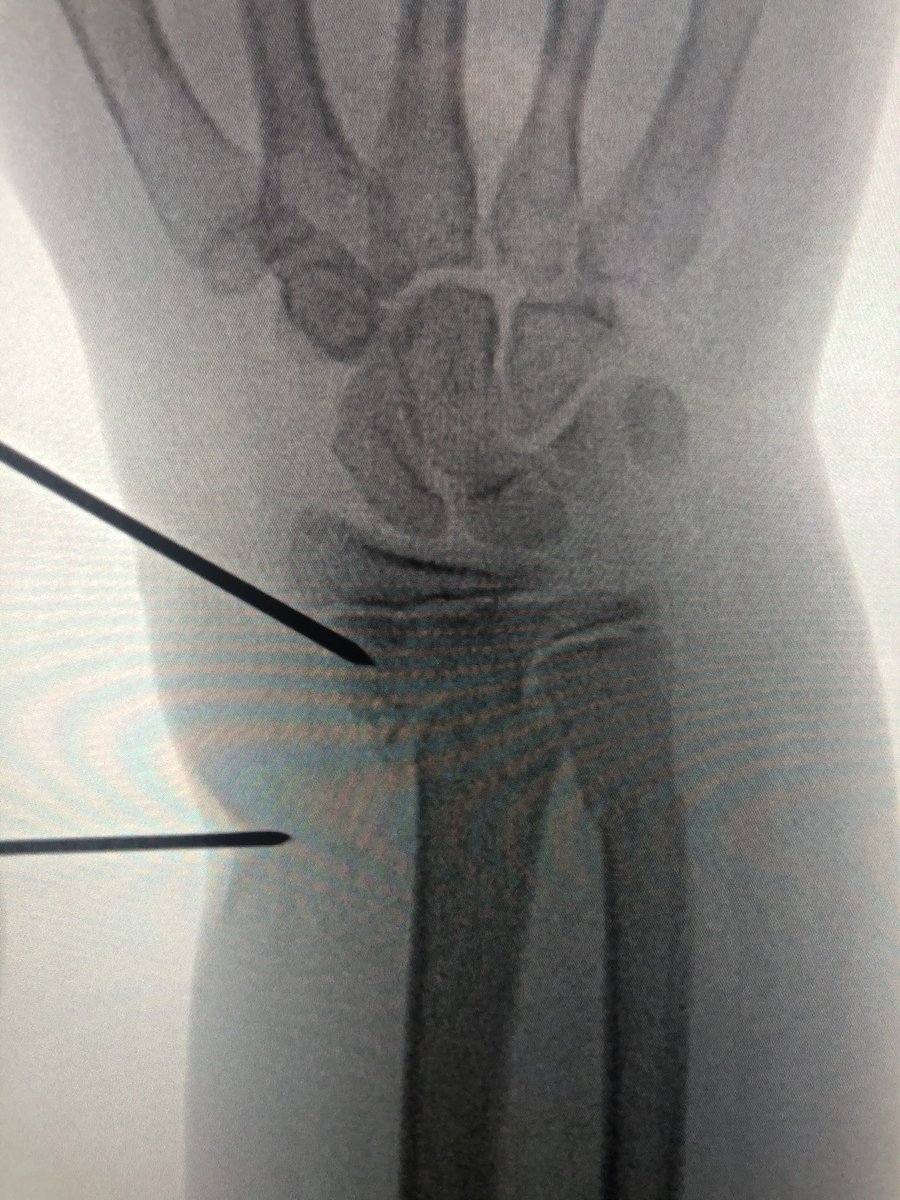

[3/4] This is my reduction, manually on distal fragment, with my other hand on threaded wire pulling it radially, using it as joystick. Once lined up, since distal wire already in and pointing in correct direction, all my resident has to do is fire wire into proximal fragment.

[4/4] I didn’t I think one wire was going to be enough, so I removed joystick and then placed another smooth wire proximal to distal; there wasn’t much room in there because trying not to get the physis. Cast, then pins pulled in clinic at 4 weeks. Xrays done at 2, 4, 8 weeks.